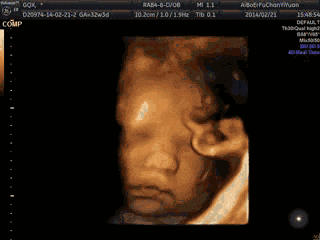

第1张图:上蹿下跳

在妈妈还没明显觉察到胎动时,宝宝在子宫里其实过得非常惬意。子宫对他来说空间足够,他会在里面“上蹿下跳”,甚至在做B超时,因为动得太厉害,有时连B超都难以捕捉清晰的数据。

所以妈妈去做B超前,可以准备一些食物,如果宝宝不配合,医生可能会让妈妈走动一下,等宝宝安静或转过身时再查看。